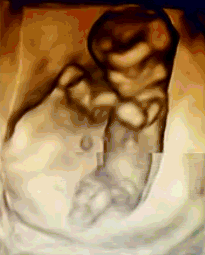

NT是胎儿颈部半透明膜的缩写,是10~13孕周围绕在胎儿颈项后部流动性的半透明蛋白膜。它的厚度与胎儿DS缺陷正相关,并可以通过超声成像测量。

NT排畸检查是指胎儿颈后部皮下组织内液集聚的厚度的检查。通过B超测定颈项透明层厚度,便于及早发现唐氏儿和先天性心脏病的胎儿,并及时予以干预。NT检查是检查胎儿有没有先天愚型,是优生优育必要的检查。